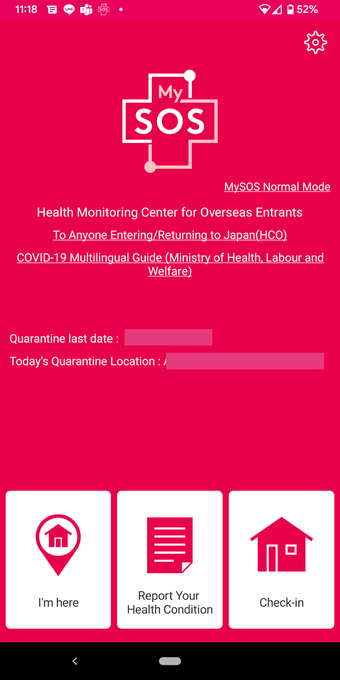

MySOS เป็นแอปพลิเคชันบนมือถือที่ช่วยให้ผู้ใช้เข้าถึงข้อมูลและบริการที่เกี่ยวข้องกับสุขภาพและการดูแลรักษาสุขภาพในประเทศญี่ปุ่น มันถูกออกแบบมาเพื่อให้การช่วยเหลือในกรณีฉุกเฉินทางการแพทย์และรองรับการดูแลสุขภาพและการบริการฉุกเฉิน

เมื่อคุณใช้ MySOS คุณสามารถเข้าถึงข้อมูลและบริการที่เกี่ยวข้องกับสุขภาพและการดูแลรักษาสุขภาพในประเทศญี่ปุ่นได้ คุณสามารถส่งคำขอความช่วยเหลือไปยังผู้ที่คุณไว้วางใจ เช่นครอบครัวหรือเพื่อนของคุณ คุณยังสามารถยืนยันตำแหน่งของ AED หรือโรงพยาบาลที่คุณต้องการไปเยี่ยมชมและส่งคำขอความช่วยเหลือไปยังผู้ที่คุณไว้วางใจได้